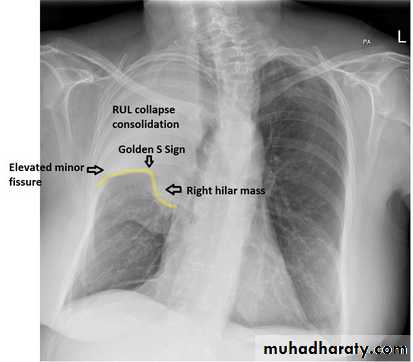

The opacification is sited anterior to the obliq- fissure-the position of the upper lobe.RLL collapse - PA.

•Nodular (coin) lesion in the left upper lung with irregular edge (most probably cancinoma